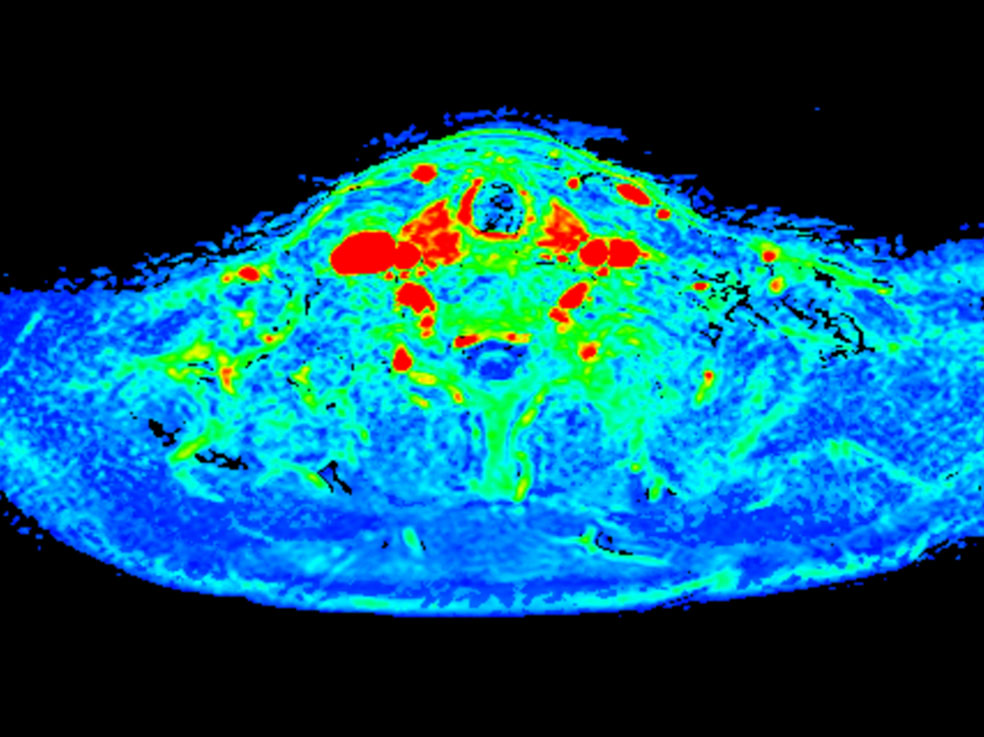

Axial T1w mDIXON XD FFE (area under the curve)